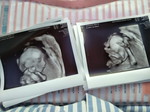

แตกแล้วค่าา 39week

น้องมินนี่ รายงานตัวค่ะ นน.แรกเกิด 3402 กรัม เกิดวันที่ 15/07/2020 เวลา 12:06 น. มะม๊าคลอดธรรมชาติค่า ... ปวดท้องตอนตี5ครึ่ง 8โมงน้ำเดิน เที่ยงคลอดเลยค่ะ ความเจ็บปวดที่งดงามมาก 👧🏻❤